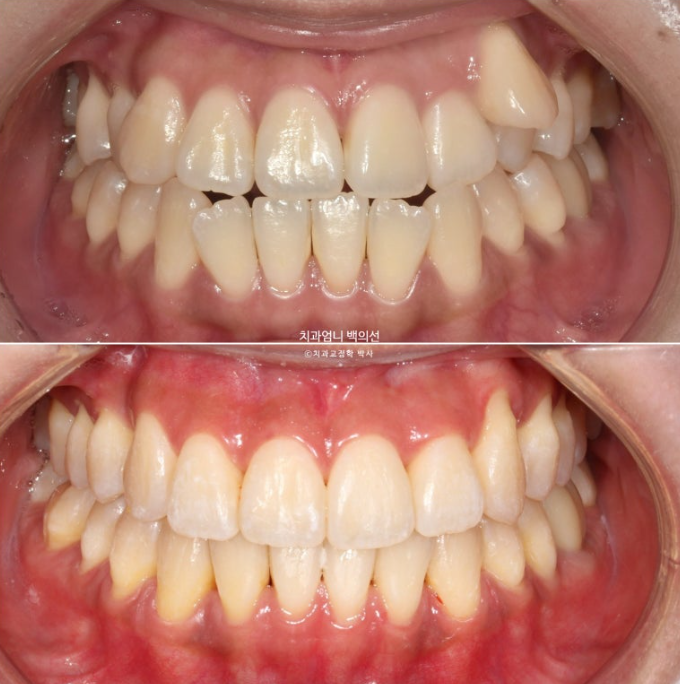

23.09~25.03

초진 3mm의 중심선 불일치가 해결되었습니다.

윗니가 아랫니를 덮는 양이 안정적입니다.

잘 내려와준 덧니입니다.

앞니가 거꾸로 물리던 부분도 정상교합을 찾았습니다